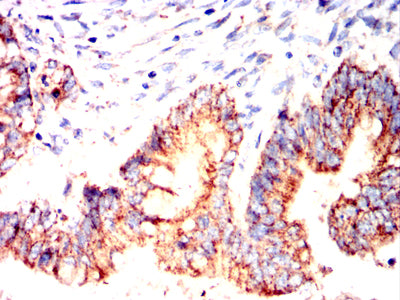

Immunohistochemical analysis of paraffin-embedded human colon cancer tissues using MUC13 mouse mAb with DAB staining.

Immunohistochemical analysis of paraffin-embedded human rectal cancer tissues using MUC13 mouse mAb with DAB staining.